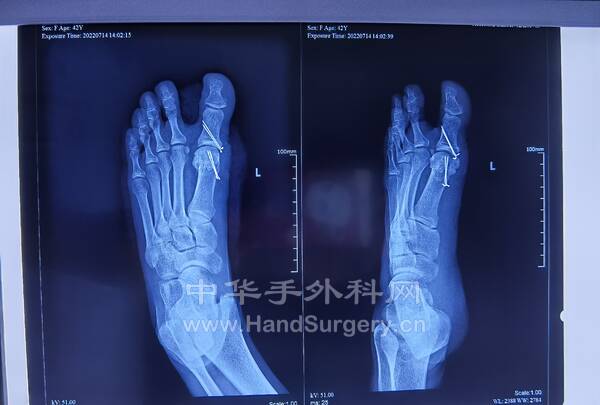

跟距骨桥,拇外翻患者行距下关节融合术,拇外翻矫形术后8周复查,